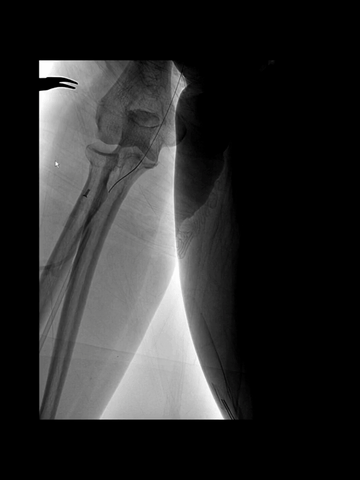

右股动脉穿刺置8F短鞘,5F长多功能管(125cm)和6F长鞘(90cm,Cook)组成同轴,导丝导引下5F管头端进入右锁骨下动脉。

长鞘跟进到右锁骨下动脉近端。

5F管沿导丝送至右腋动脉,经此管送入一.018"导丝(Command 18),其头端置于右肱动脉远端,保留导丝,交换出5F管,.018"导丝作悬吊支撑用。

微导管(Rebar 18)配合微导丝(Command 14)尝试超选右椎动脉,但微导丝头端难以通过V1的曲折管腔;后长鞘内衬一4F长多功能管增强支撑和指向性,但微导丝仍然难以克服右V1的曲折。

微导丝头端改塑形状后,还是克服不了右V1曲折。

穿刺右桡动脉,置入6F桡鞘;4F长多功能管(125cm)和Navien 072(105cm)组成同轴,泥鳅导丝导引下,4F管头端行至右锁骨下动脉近端。

经4F管送入先前的微导管微导丝,微导丝顺利通过右V1曲折,跟进微导管过程中,支撑不足,弹回右锁骨下动脉。

调整4F头端位置和方向,经数次尝试后,微导丝再次进入右椎动脉,并克服V1曲折上高到V3。

后续微导管顺利跟进到V3,撤出Command 14导丝,送入0.18"导丝(Commmand 18)导丝增强支撑,此时中间管沿微导管微导丝推送到V3。

中间管被进一步推高到V4近端。